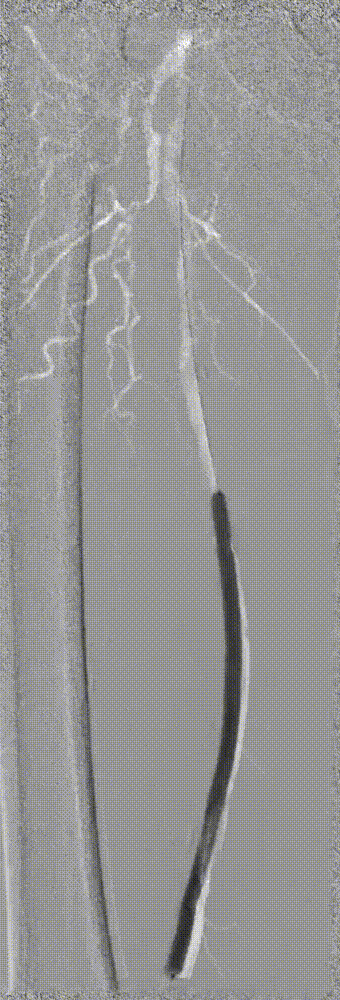

因患者股浅动脉及腘动脉狭窄闭塞段均严重钙化,选择使用振波球囊(6mm*80mm、5mm*80mm)

分别对股浅动脉、腘动脉狭窄闭塞段扩张(球囊至4atm,3级振波强度3个循环,5级振波强度3个循环);球囊切迹逐渐消失

IVUS提示病变段仍有局部重度狭窄,遂选择最新上市的”始祖鸟”紫杉醇药物涂层球囊(5*150mm、6*150mm )对残余狭窄进行扩张

IVUS提示病变段仍有局部重度狭窄,遂选择最新上市的”始祖鸟”紫杉醇药物涂层球囊(6*150mm、 5*150mm ) 分别对股浅动脉、腘动脉、胫腓干动脉逐段扩张,压力至工作压维持3分钟。